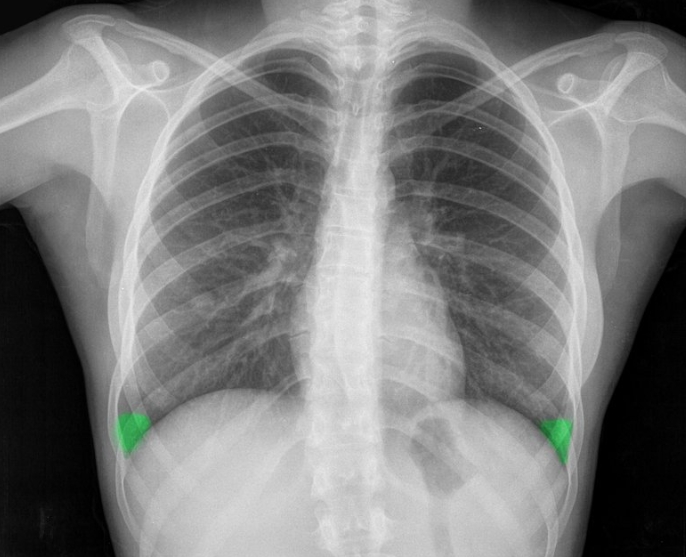

엑스레이는 가볍고 빠른 검사예요. 병원에서 기침이나 흉통이 있으면 가장 먼저 찍는 사진이죠. 하지만 엑스레이는 가슴 속 장기를 한 번에 찍기 때문에, 여러 구조가 겹쳐 보입니다. 그만큼 정확한 구분이 어렵고, 미세한 결절이나 염증은 지나치기 쉽습니다.

흉부CT는 이야기가 달라요. 얇게 자른 단면을 수백 장 촬영하기 때문에, 작은 병변도 놓치지 않습니다. 마치 산 전체를 한 장의 사진으로 보는 엑스레이와 달리, CT는 나무 한 그루 한 그루를 자세히 보는 느낌이에요. 예전에 병원에서 일했던 친구 말로는, 엑스레이에 아무 이상이 없던 환자가 CT에서 폐암 초기 진단을 받은 경우도 많았다고 합니다. 그만큼 CT는 정밀한 탐색 도구입니다.